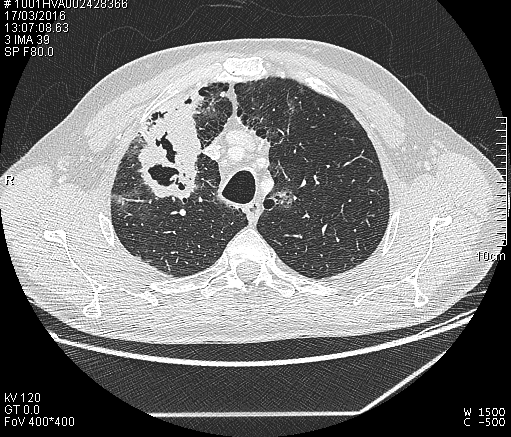

Obtenemos las siguientes imágenes en distintos planos:

Vemos que la estructura cavitada posee una pared muy gruesa, más típica de un proceso neoplásico, y una cavidad hipodensa. Confirmamos su localización en el lóbulo superior derecho y anterior. Descartamos proximidad a vasos y estructuras mediastinicas, así como invasión de la pared torácica. Y lo mas importante es que apreciamos que el bronquio principal mas proximal a la masa cavitada, el bronquio anterior del lóbulo superior derecho, se encuentra amputado cuando llega a la masa y no comunica con la cavidad del interior de la masa,